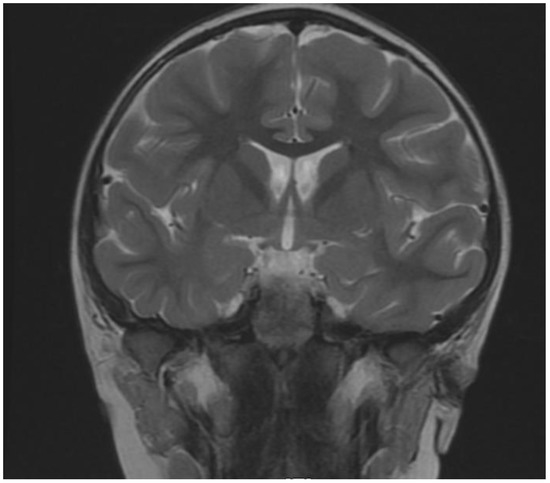

| Brain MRI | |

| no | Polymicrogyria |

| no | Corpus callosum hypoplasia/agenesis |

| no | Ventricular enlargement |

| no | Key-hole shaped temporal horns |

| no | Colpocephaly |

| no | Delayed myelination/decreased cortical white |

| no | Small pons |

| no | Small interior vermis |

| yes | Changes in temporal lobe- cyst |